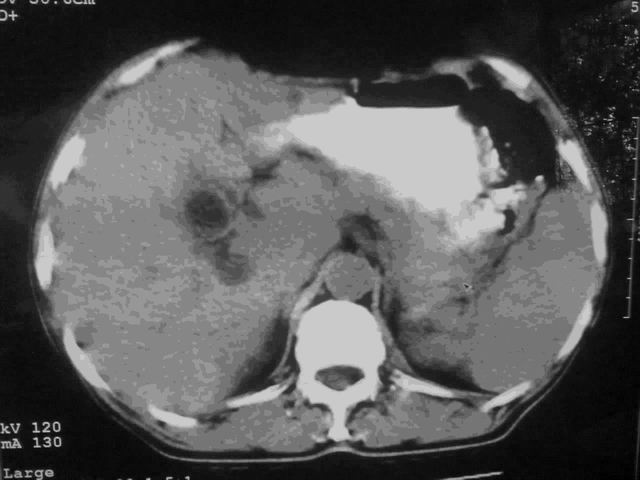

我这个考考大家眼力,看看是升结肠ca还是降结肠ca

好象是横结肠占位肝转移,胰头占位?【伙计,您的片也真够意思】

伪影太多,考虑降结肠癌伴肝转移,胆囊炎

伪影太多,考虑升结肠癌伴肝转移,胆囊炎

考虑升结肠癌伴肝转移;胆囊炎。

结肠占位并肝及腹膜后淋巴结转移。

考虑升结肠癌伴肝转移;胆囊炎